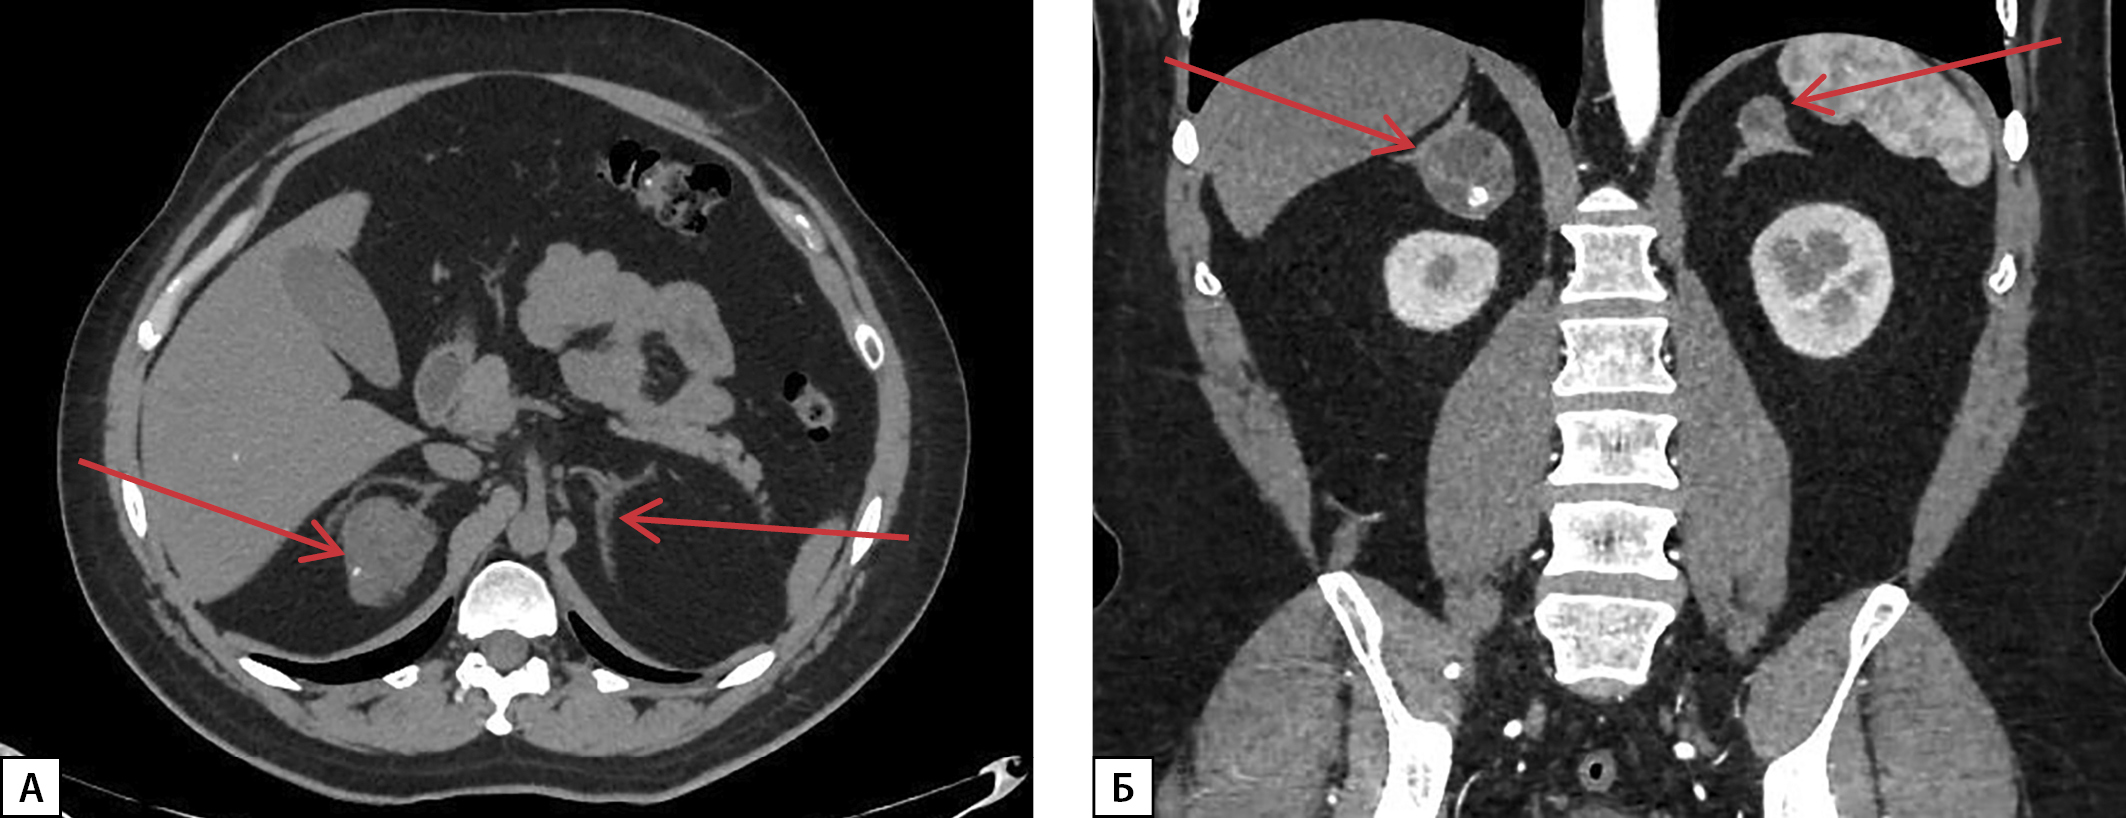

В связи с жалобами на тянущие боли в правом подреберье выполнена МСКТ забрюшинного пространства: оба надпочечника деформированы, неравномерно утолщены за счет разнокалиберных узелков в структуре размерами до 5–20 мм, неравномерно накапливают контрастный препарат; в медиальной ножке правого надпочечника обнаружено образование с бугристыми четкими контурами размерами до 50х42х42, неоднородное по структуре, с наличием кальцинатов, плотностью 26-86-157-93 HU (нативная — артериальная — венозная — отсроченная фазы соответственно), абсолютный коэффициент вымывания — 48,9%, относительный коэффициент вымывания — 40,8%, в левом надпочечнике — аналогичное образование размерами 22х25х18 мм (рис. 3).

Рисунок 3. МСКТ надпочечников с контрастным усилением:

А — нативная фаза — в медиальной ножке правого надпочечника образование с бугристыми четкими контурами, неоднородное по структуре, с наличием кальцинатов (красная стрелка); Б — артериальная фаза — в левом надпочечнике аналогичное образование (белая стрелка); В — венозная фаза; Г — отсроченная фаза — оба надпочечника деформированы, неравномерно утолщены за счет разнокалиберных узелков в структуре (красные стрелки).

По данным МСКТ надпочечников от 25.06.2024 г., надпочечники неравномерно утолщены за счет узелков плотностью от -20 ед. Н до 20 ед. Н, сливающихся в конгломераты максимальным размером справа 44х38х32 мм (с кальцинатами и жировыми включениями), слева — 22х15х18 мм. При сравнении с исследованием от 16.10.2023 г. отмечалось уменьшение размеров конгломератов узлов и толщины надпочечников (рис. 4).

Рисунок 4. МСКТ надпочечников с контрастным усилением:

А — нативная фаза, Б — артериальная фаза — отмечается уменьшение размеров конгломератов узлов, уменьшение толщины надпочечников (красные стрелки).